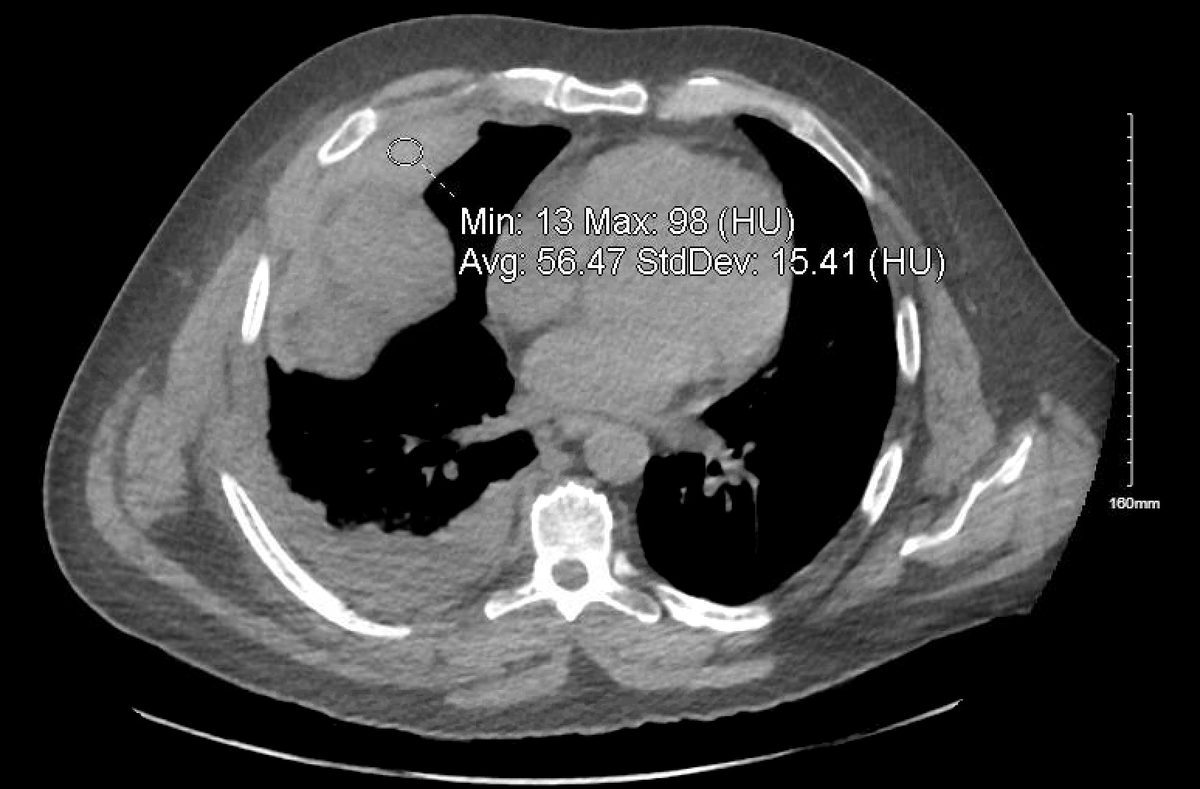

@ASanchez_PS I am seeing an homogenous mass around the right paraspinal area, infiltrating the bone. Wondering if it could be any soft tissue sarcoma???

@davserantes What I was thinking … IgG level almost 3000. Light chain ratio slightly off. Will update when SIFE comes back